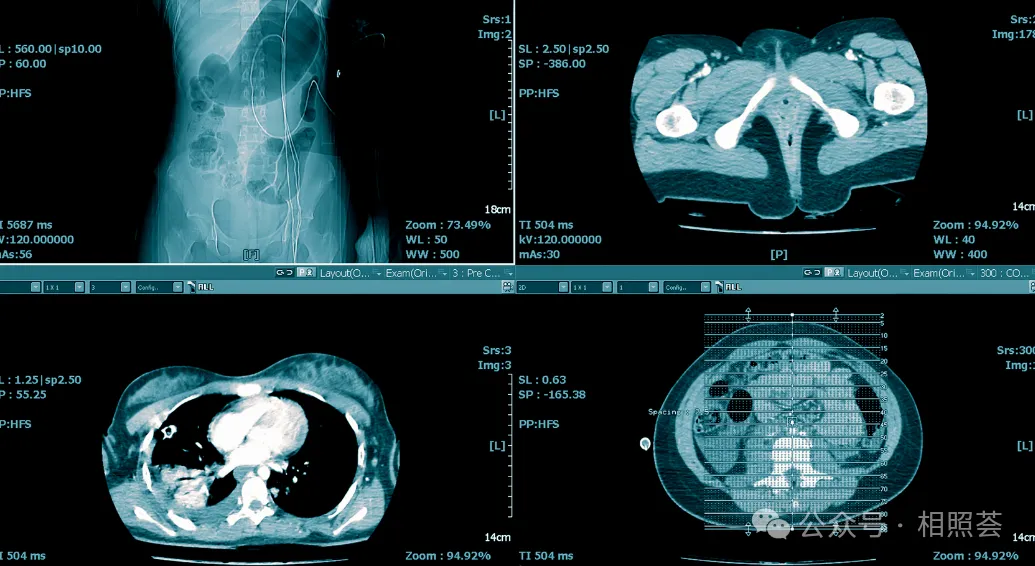

患者必看!北京重疾与癌症诊疗权威医院指南,这样选才不迷茫!

在北京,医疗资源密集,尤其是针对重大疾病及癌症的诊疗,多家医院凭借其卓越的医疗技术、权威的专家团队和先进的诊疗设备,成为患者心中的“生命守护者”。本文将为您详细介绍几家在治疗重疾及癌症方面具有显著优势的权威医院,帮助您在面对疾病时做出更明智的选择。一、中国医学科学院肿瘤医院:国家癌症中心的坚实后盾医院概况:中国医学科学院肿瘤医院,始建于1958年,是国家癌症中心依托单位,也是国家肿瘤临床医学研究中